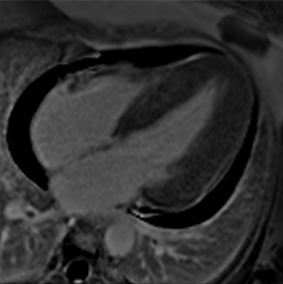

Table 3 summarises a suggested CMR scan protocol for the diagnosis of presumed HHD and differential diagnosis of patients with a “thickened left ventricle”.

Table 3.

The cardiovascular magnetic resonance protocol used for assessment of hypertensive patients. The described protocol can be acquired within 45–50 min. Images are examples from patients with hypertensive heart disease.

Similar to echocardiography, LV geometry can be assessed using relative wall thickness (RWT) and CMR-specific normal values for LV myocardial mass (Figure 2). LA dimensions can be assessed with Simpson’s biplane or area-length methods from the standard views, or more precisely with a volumetric assessment using an atrial short-axis stack. LA enlargement is a reliable marker of diastolic dysfunction (chronically elevated LV filling pressures) in the absence of mitral valve disease [31]. The recently introduced left atrial coupling index (LACI) is a ratio of the indexed left atrial end-diastolic volume (LAVI) in relation to the left ventricular end-diastolic volume (LVEDVI) [32]. This ratio may offer prognostic information regarding cardiovascular events such as atrial fibrillation, heart failure, and coronary artery disease-related death.